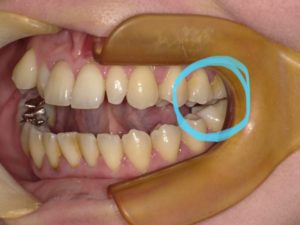

横から見るとこんな感じです🙌🏻

この歯並びは、「開咬(かいこう)」という不正咬合です。

前歯が噛み合わないため、食べ物を噛み切る事が難しくなります。